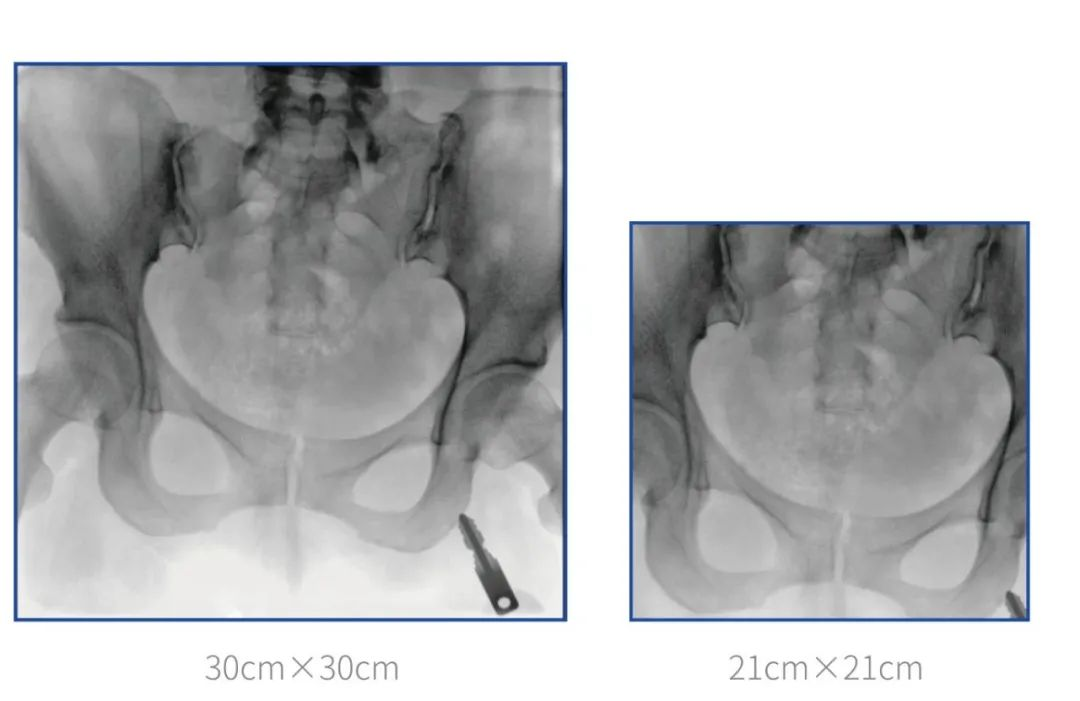

普愛醫療堅持自主研發、持續創新,從臨床需求出發,推出了大視野,能夠呈現更多圖像細節的大平板一體式C形臂。大平板一體式C形臂配置30cm×30cm平板探測器,對于諸如骨盆雙側骨折類型手術或骨盆后環內固定術具有應用優勢,一次曝光可獲取全部骨折部位影像,可簡化曝光流程,提高手術效率!